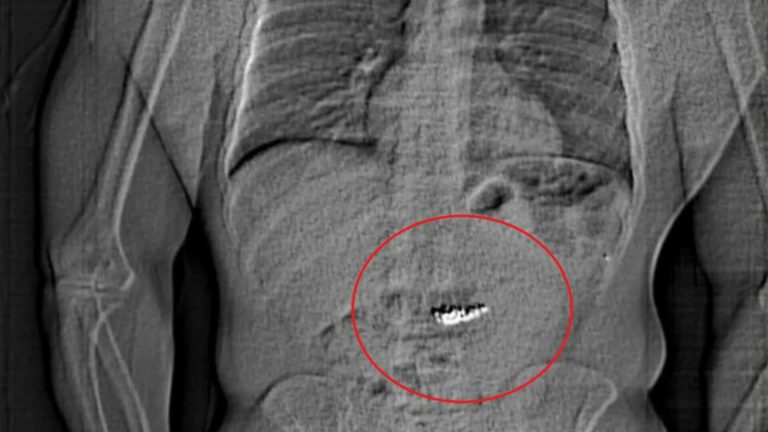

O strategie riscantă pentru un jaf spectaculos Jaythan Gilder, un bărbat de 32 de...